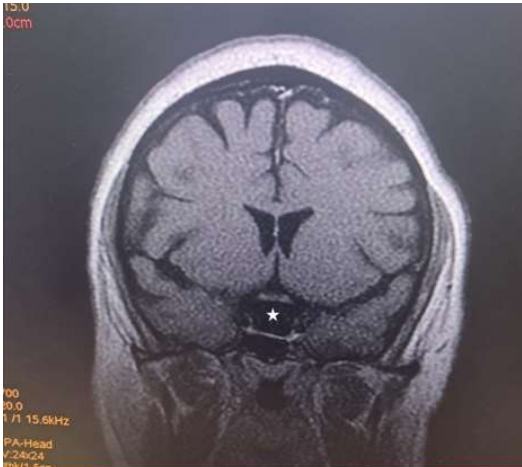

Magnetic Resonance Imaging (MRI) revealed expansion of the sella with a well-defined fairly rounded lesion measuring 15 X 14 X 15mm (width X AP X H). It is hypointense on T1W, hyperintense on T2W and suppressed on FLAIR sequence. Rim enhancement is seen post contrast. The mass is inseparable from the optic chiasma suggestive of compression.

Figure 6: Coronal T1W image of the brain showing a hypointense rounded intrasellar mass lesion (white asterisk).

Due to its high soft tissue resolution, Magnetic Resonance Imaging (MRI) is the primary diagnostic technique for RCC9. It also determines the cystic content and fluidity of the cyst which is useful in planning for subsequent patient’s management10. Fifty percent are hyperintense on T1W (due to high protein content) while 50% are hypointense. On T2W, 70% are hyperintense, 30% iso or hypointense and 20% have hypointense rim. T1W Post contrast images usually show no enhancement. However, a thin enhancing rim may be seen when cyst wall infection is present [19-20]. The case presented revealed expansion of the sella with a well-defined fairly rounded lesion measuring 15 X 14 X 15mm (width X AP X H). It is hypointense on T1W, hyperintense on T2W and suppressed on FLAIR sequence. Rim enhancement is seen post contrast. The mass is inseparable from the optic chiasma suggestive of compression. The appearance of the cyst confirmed no haemorrhage or debris within the cyst. However, the rim enhancement suggest inflammation of the cyst as explained in the text. The finding of optic chiasma compression may explain the visual impairment and the bitemporal hemianopia seen in the patient.